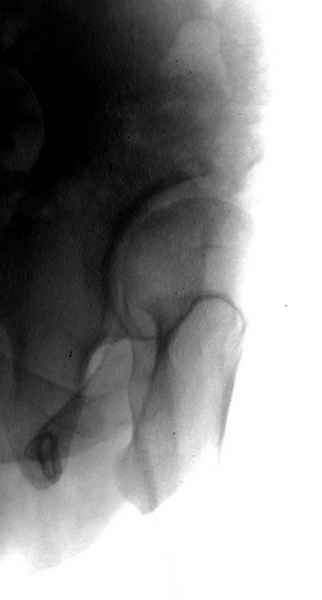

Картина типичной эволюции дисплазии сустава "кистовидная перестройка", на фоне неправильного взаймоотношения сустава "да тут угол Виберга 0 градусов" на вершине наибольшей нагрузки в вертлужной впадине образовался участок разрежения, "киста", в последующем через этот участок образуется перелом - стадия фрагментация дисплазии.

Неоднократные обсуждения на форуме "пропущенных переломов" показывает, что короткие урезанные снимки приводят к ошибке, тем более у данного больного для решения тактики лечения необходимо детальное исследование суставов.

А для данного случая, необходим прямой снимок таза с отдельными суставами, также включить боковые снимки сустава, немаловажно знание покрытия головки спереди.